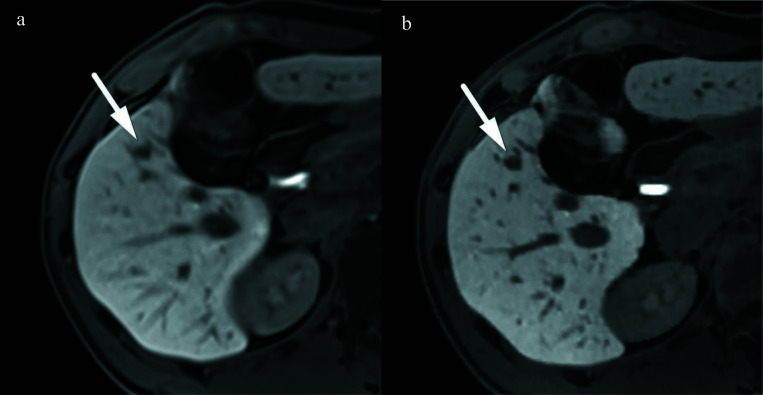

目的:评估在钆醋酸增强肝脏磁共振成像中使用压缩传感(CS)的屏气(BH)高分辨率(HR)T1加权梯度回波肝胆相(HBP)成像与使用平行成像(PI)的标准HBP成像的可行性:研究纳入了122例HBP低密度肝肿瘤患者,他们同时接受了CS的HR HBP成像和PI的标准HBP成像。两位放射科医生评估了肝脏边缘锐利度、肝脏血管清晰度、胆管清晰度、图像噪声和整体图像质量,以及HR和标准HBP成像的病灶清晰度和由HBP图像重建的对比增强(CE)磁共振胆管造影(MRC)图像质量。作为定量分析,还测定了肝脏的信噪比和肝脏与病变信号强度比(LLSIR):结果:使用 CS 进行 HR HBP 成像时,肝脏边缘锐利度、肝血管清晰度、胆管清晰度、整体图像质量以及病变清晰度和 LLSIR 均显著高于标准 HBP 成像(P 均<0.001)。使用 CS 进行 HR HBP 成像重建的 CE-MRC 图像质量也明显高于标准 HBP 成像(P < 0.001)。相反,标准 HBP 成像中肝脏的信噪比明显高于使用 CS 的 HR HBP 成像(P < 0.001):结论:与标准 HBP 成像相比,带 CS 的 BH HR HBP 成像可在不延长采集时间的情况下提高整体图像质量、病灶清晰度和 CE-MRC 可见度。

Results: The liver edge sharpness, hepatic vessel conspicuity, bile duct conspicuity, and overall image quality as well as the lesion conspicuity and the LLSIR on HR HBP imaging with CS were significantly higher than those on standard HBP imaging (all of P < 0.001). The image quality of CE-MRC reconstructed from HR HBP imaging with CS was also significantly higher than that from standard HBP imaging (P < 0.001). Conversely, the SNR of liver in standard HBP was significantly higher than that in HR HBP with CS (P < 0.001).

Conclusion: BH HR HBP imaging with CS provided an improved overall image quality, lesion conspicuity, and CE-MRC visualization when compared with standard HBP imaging without extending the acquisition time.